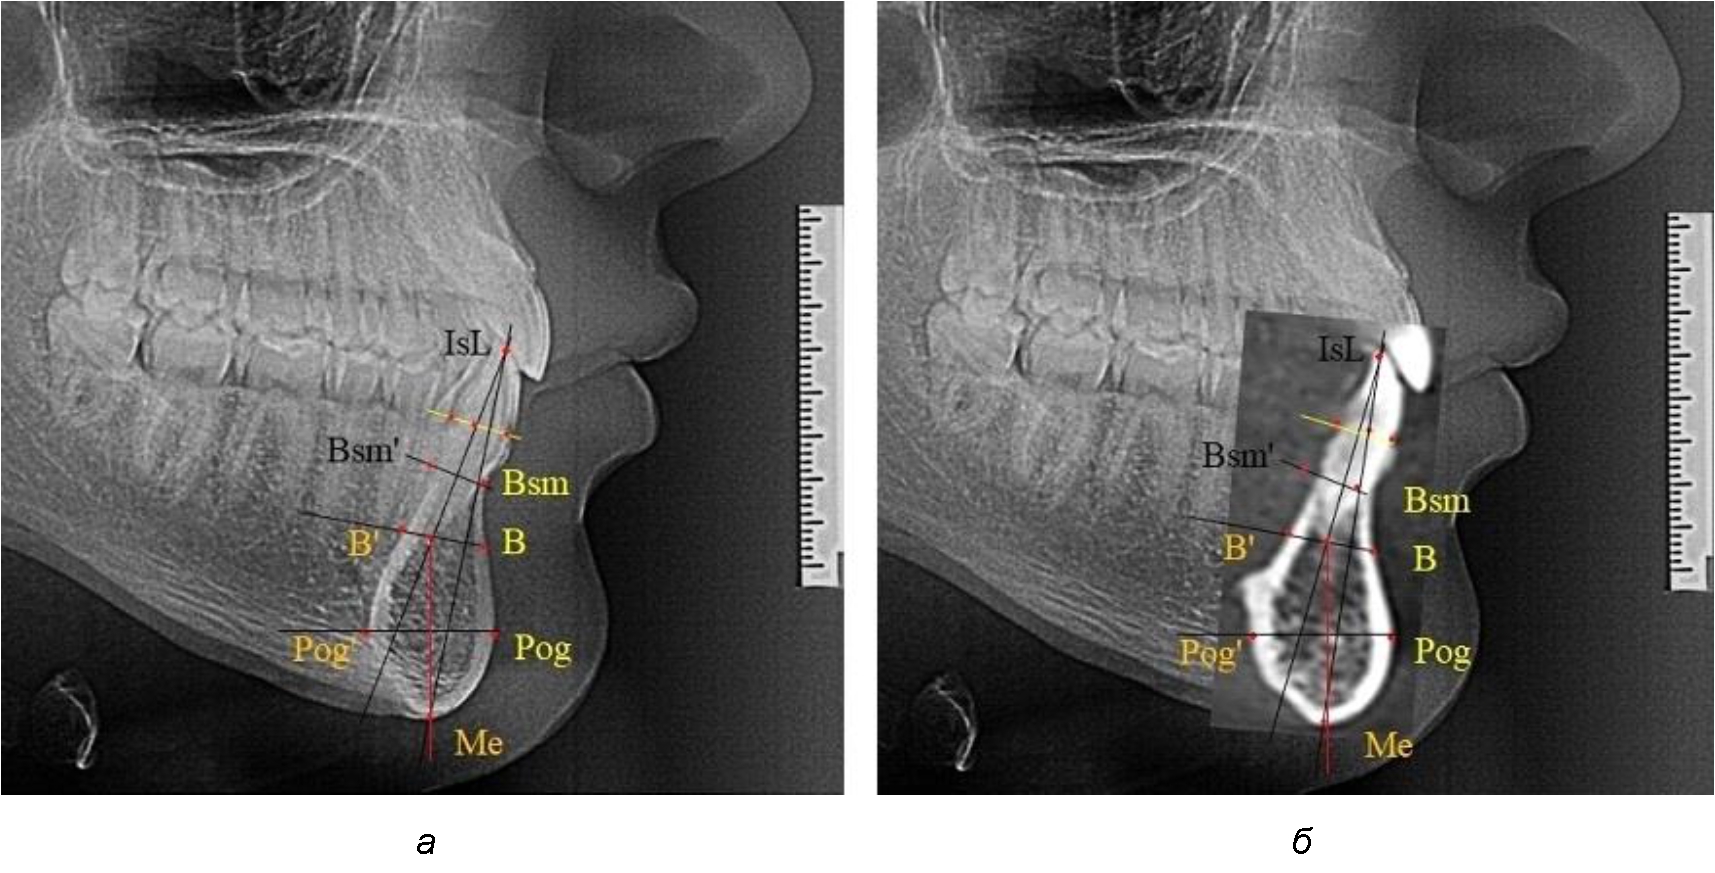

На режущем крае нижнечелюстного резцового сегмента устанавливалась точка, обозначаемая как IsL.

Определяли положение цервикальных точек резцов на вестибулярной и лингвальной поверхностях, которые соединяли цервикальной линией. Условная срединную вертикаль зуба соединяла резцовую точку IsL с серединой цервикальной линии и, как правило, доходила до апикальной точки, которую обозначали как Ap. Линия IsL–Ap определяла высоту зубоальвеолярной части резцового нижнечелюстного сегмента. Определяли высоту коронки и корня зуба. Кроме того, на вестибулярной поверхности зубочелюстного сегмента отмечали точку наибольшей вогнутости альвеолярной части, которая обозначалась как супраментальная точка Downs (Bsm). Измерялось расстояние IsL–Bsm, которое служило для определения проекции супраментальной точки Downs на язычную поверхность сегмента и обозначалась как точка Bsm'.

Проекцию верхушки корня резца на кость обозначалась как точка B нижнего апикального базиса по Schwarz. Соединяли апикальную точку с точкой нижнечелюстного апикального базиса линией, которая доходила до язычной поверхности подбородочного выступа и определяла положение точки B'. Таким образом, в зубоальвеолярной части сегмента выделялись две зоны: верхняя и нижняя, с последующим измерением по вертикали. При этом, как правило, верхняя зона была представлена компактной костной тканью, а в нижней зоне определялось наличие губчатой ткани между компактной пластинкой и стенкой альвеолы.

На нижнем контуре подбородочного выступа определяли положение ментальной точки Me. Линия, соединяющая апикальную точку с ментальной, определяла высоту подбородочного выступа тела нижней челюсти. Высота зубочелюстного сегмента IsL–Ме измерялась от резцовой до подбородочной точки. Вертикальная линия Ap–Me делила подбородочный выступ на две части: переднюю и заднюю (рис. 1).

Рис. 1. Ориентиры для исследования нативных препаратов (а) и рентгенограмм (б) резцового нижнечелюстного сегмента

Сагиттальные размеры зубоальвеолярной части сегмента определялись между точками Bsm и Bsm', в апикальной части сегмента – B и B'. В подбородочной части сегмента из передней выступающей точки подбородка Pog проводили линию перпендикулярно к линии Ар–Ме с определением точки Pog'. Расстояние Pog–Pog' определяло ширину подбородочного выступа.

При необходимости и/или возможности проведения КЛКТ-исследования проводили анализ с сопоставлением фрагмента, что повышало точность диагностических мероприятий (рис. 2).

Рис. 2. Фрагменты ТРГ с ориентирами для измерения параметров резцового сегмента (а) и с наложением фрагмента КЛКТ (б)